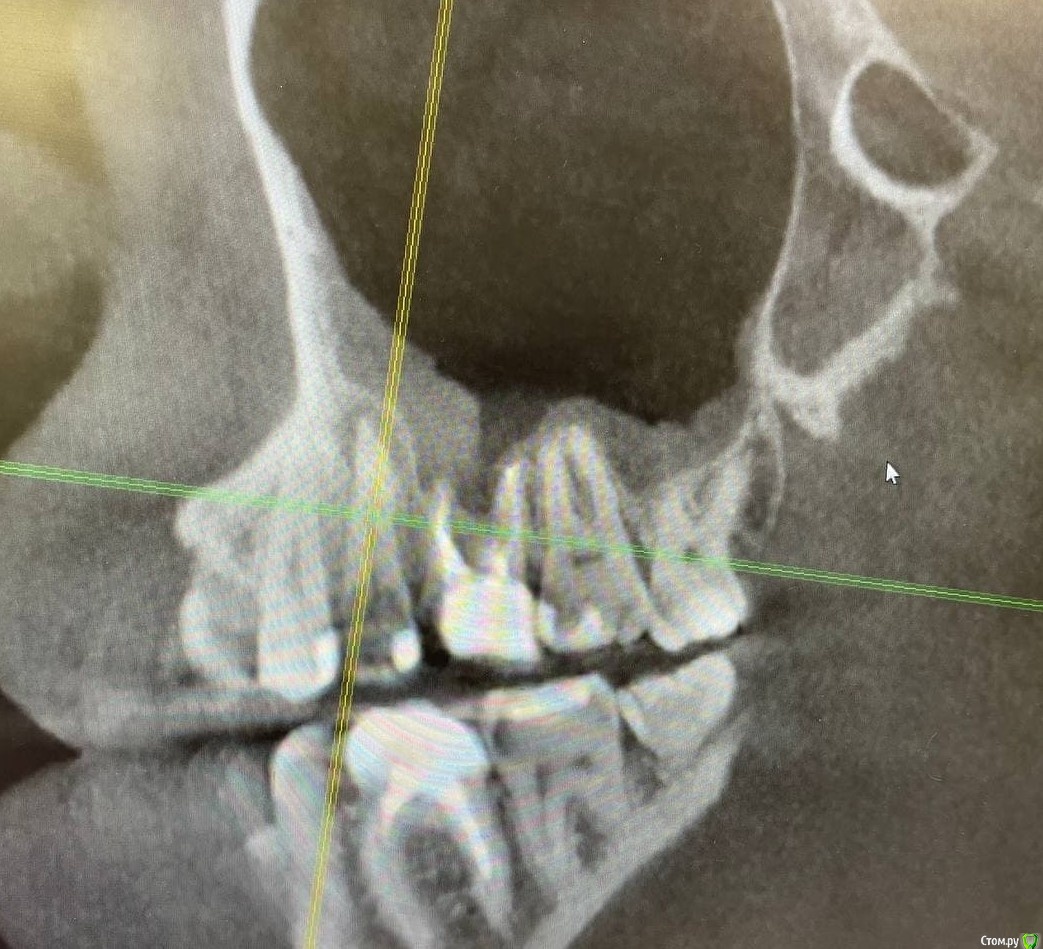

1586Doc Опубликовано 17 января, 2021 Автор Поделиться Опубликовано 17 января, 2021 еще один кейс.Утолщение слизистой гайморовой, хронический процесс на 25.26 зубахконтроль клкт через 8 месяцев Ссылка на комментарий

1586Doc Опубликовано 17 января, 2021 Автор Поделиться Опубликовано 17 января, 2021 первые 3 фото, ретрит 14 зуб4.5 фото 45 зуб. 4 Ссылка на комментарий